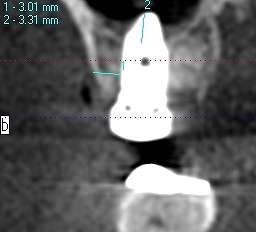

術前術後のCTになります

術前術後のCTになります